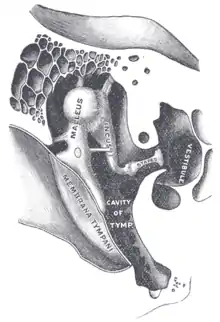

L'enclume ou incus[1] est un des trois osselets de l'ouïe situé dans l’oreille moyenne. Il se place entre le marteau en dehors et l'étrier en dedans.

Le corps de l'enclume se situe dans le récessus épitympanique. Il a grossièrement la forme d’un cube aplati de dehors en dedans. Sa face antérieure concave porte la facette articulaire du corps de l'enclume qui répond à la facette articulaire du marteau pour former l'articulation incudo-malléaire.

Du fait de sa position centrale, l'incus s'articule avec les deux autres osselets, le marteau et l'étrier. Aucun muscle n'est relié à l'enclume, mais il est maintenu par deux ligaments, l'un supérieur et l'autre postérieur, dans la cavité tympanique.

Articulation incudo-malléaire

Le corps de l'enclume s'articule avec la tête du marteau par emboîtement réciproque. Les deux surfaces articulaires sont recouvertes d'une fine couche de cartilage hyalin, et un ménisque inter-articulaire qui s'attache à la partie médiale de la capsule s'étend plus ou moins de dedans en dehors entre les deux surfaces articulaires. Une capsule articulaire recouverte en dedans de synoviale maintient les deux os ensembles.

Articulation incudo-stapédienne

L'enclume s'articule avec l'étrier par son processus lenticulaire, extrémité inférieure de sa branche verticale. Cette articulation est de type énarthrose : la surface arrondie de l'os lenticulaire est reçue dans la cavité glénoïdale de la tête de l'étrier. L'articulation est maintenue par une capsule, tapissée en dedans de synoviale et les surfaces articulaires sont recouvertes de cartilage.

L'enclume est maintenu dans l'oreille moyenne par deux ligaments. Le ligament supérieur de l'incus fixe le corps de l'enclume au tegmen tympani. Le ligament postérieur de l'incus relie l'extrémité de la branche courte à l'angle inférieur de l'orifice d'entrée de l'aditus ad antrum.